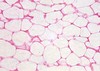

adipose CT

Structure :Adipocytes

Function Protects; stores fat; insulates

Location Subcutaneous layer; surrounding kidney and selected other organs

Structure :Adipocytes

Function Protects; stores fat; insulates

Location Subcutaneous layer; surrounding kidney and selected other organs

Relatively fewer cells and fi bers than in dense connective tissue; fibers are loosely arranged

adipose CT